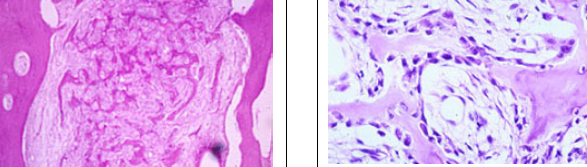

Perfectly

Osteosarcoma

highly pleomorphic cells and haphazard deposits of osteoid; anaplastic features and mitotic activity; lace-like pattern